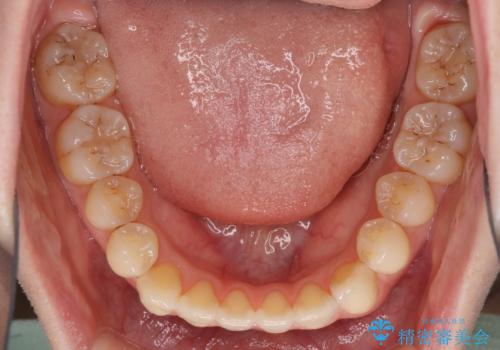

オープンバイトのインビザラインを用いた再矯正

オープンバイト(前歯の開咬)と下顎骨の偏位による不正咬合が認められました。

オープンバイトは後戻りを起こしやすいため、極力そのリスクを軽減するため、奥歯を圧下させるように治療を進めていきました。

下顎骨の偏位が顕著であったため、上下の正中を合わせることはできませんでしたが、患者様には大変満足していただきました。